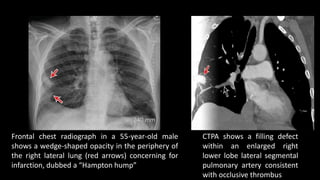

Frontal chest radiograph in a 55-year-old male

shows a wedge-shaped opacity in the periphery of

the right lateral lung (red arrows) concerning for

infarction, dubbed a “Hampton hump”

CTPA shows a filling defect

within an enlarged right

lower lobe lateral segmental

pulmonary artery consistent

with occlusive thrombus

Frontal chest radiographin a 55-year-old male shows a wedge-shaped opacity in the periphery of the right lateral lung (red arrows) concerning for infarction, dubbed a “Hampton hump” CTPA shows a filling defect within an enlarged right lower lobe lateral segmental pulmonary artery consistent with occlusive thrombus